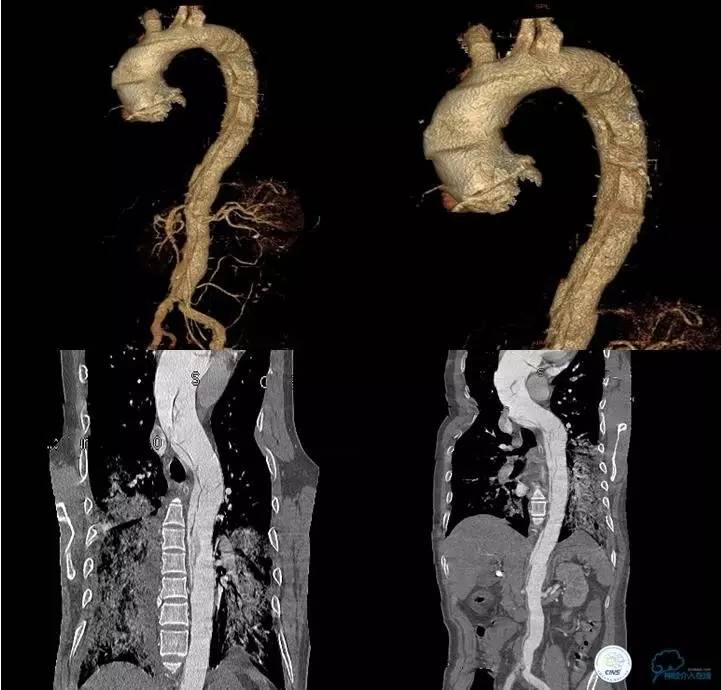

▼主动脉全程CT

诊断:

主动脉夹层 DeBakey Ⅰ型

短暂性脑缺血发作

急性心肌缺血

急性肾功能不全

急性肠系膜动脉缺血

处理意见:

继续监测血流动力学指标

绝对卧床、强效镇静与镇痛

急请血管外科会诊